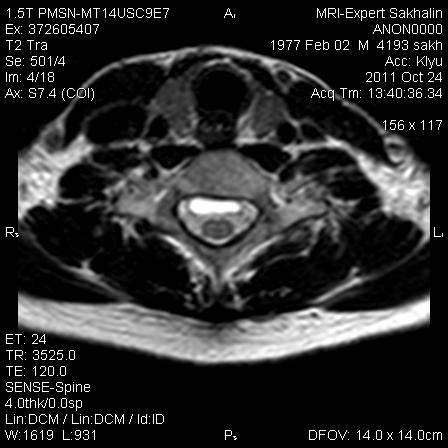

МРТ ШОП

Женщина с жалобами на боли в пояснице, но решила обследовать весь позвоночник.Травм, операций не было.Такие же изменения в грудном отделе.